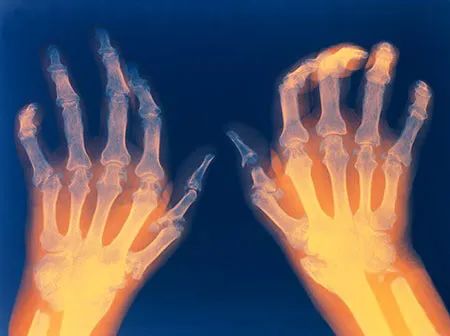

类风湿关节炎,曾一度被称为“不死的癌症”,说明这是一种对患者身体与精神都会造成严重伤害的疾病,其危害性不亚于癌症。虽然类风湿关节炎不会直接对患者生命造成影响,但反反复复的关节疼痛会令患者心烦意乱,而导致的关节变形也会严重影响生活质量。

异质性是风湿病的一大特点,类风湿关节炎也不例外地具备这个特点,即不同的患者病情严重程度千差万别。有的患者患病半年,关节就出现变形强直,有的患者患病几十年,关节功能依旧良好;有的患者服用一种药物就可以将病情控制在稳定状态,有的患者三四种抗风湿药叠加病情还是反反复复。因此,类风湿关节炎患者服药时间的长短首先取决于自身病情的严重程度。